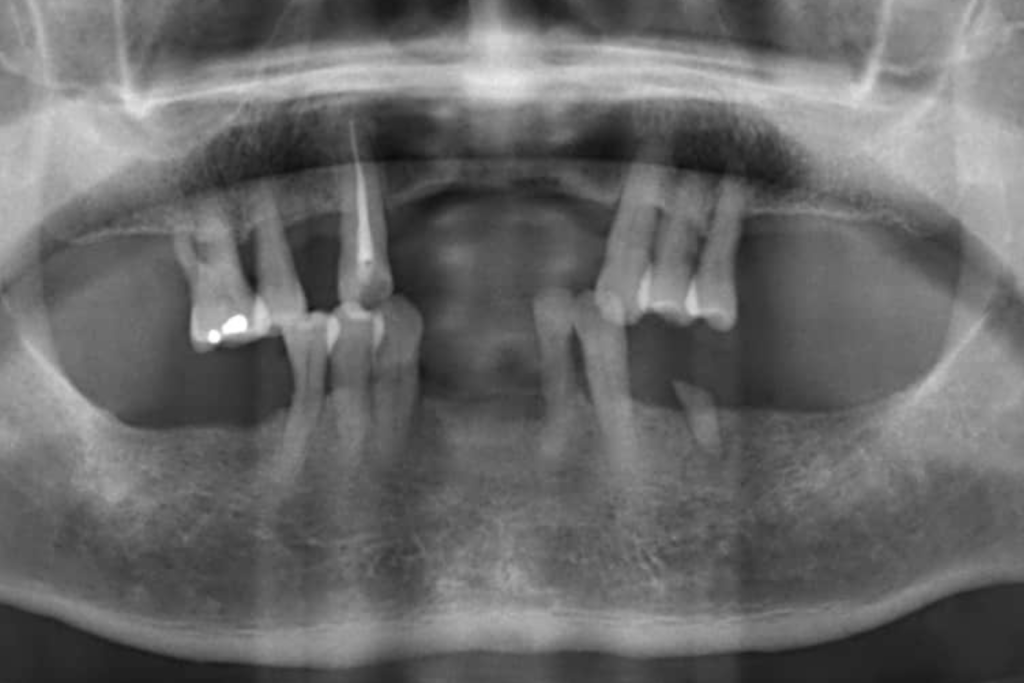

術前X光